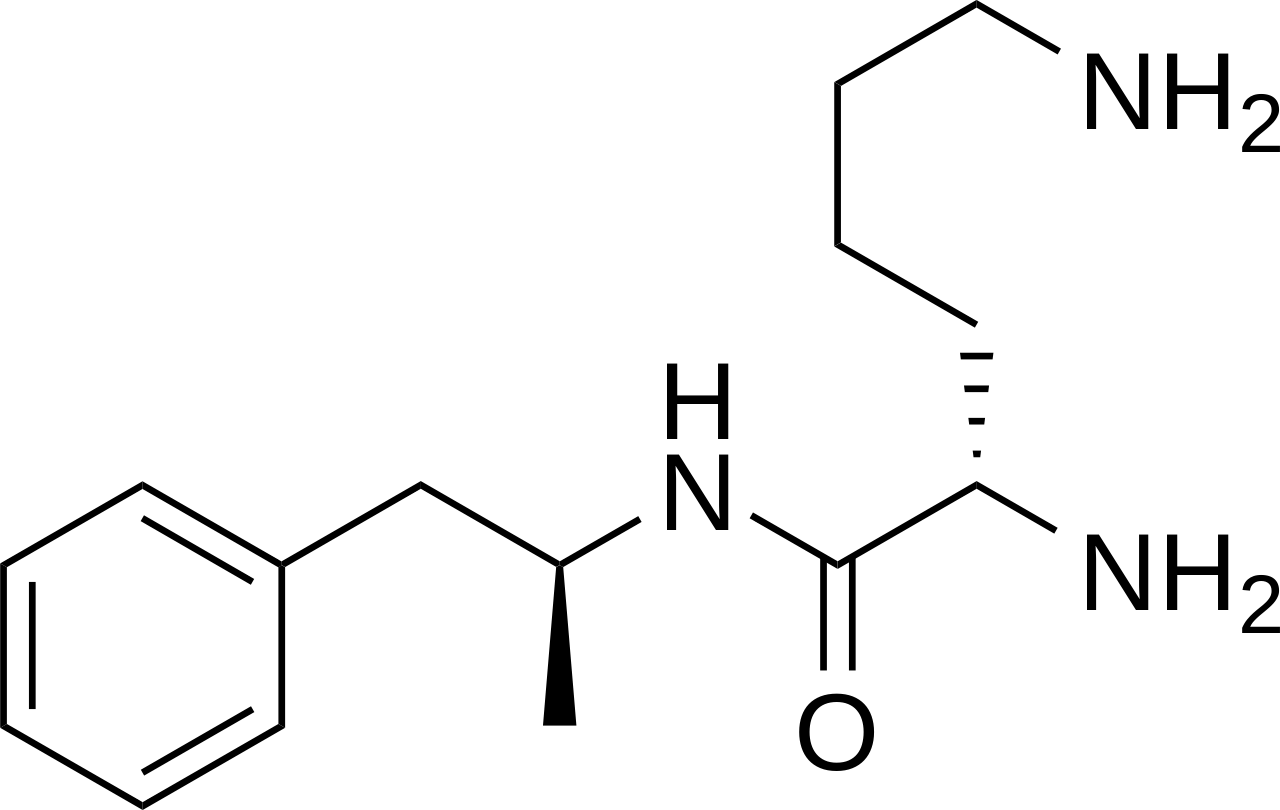

Lisdexamfetamine is a drug that can be used to help children who are affected by ADHD – attention deficit hyperactivity disorder. It has an effect on the areas of the brain associated with self-control and attention so they function better. Lisdexamfetamine is a prodrug – it is inactive. In the body it is converted to dextroamphetamine by enzymes that remove a lysine (amino acid) group. The active drug acts on neurotransmitters including serotonin, dopamine and noradrenaline in the synapses of the brain (see Cell biology). This drug is closely linked to the illegal recreational drugs known as amphetamines.

Chemical structure of lisdexamfetamine (JaGa, CC BY-SA 3.0)